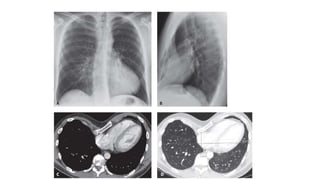

CT chest

Homogenous , high

Attenuation

Meniscoid

0-20 HU

CT chest Homogenous ,high Attenuation Meniscoid 0-20 HU